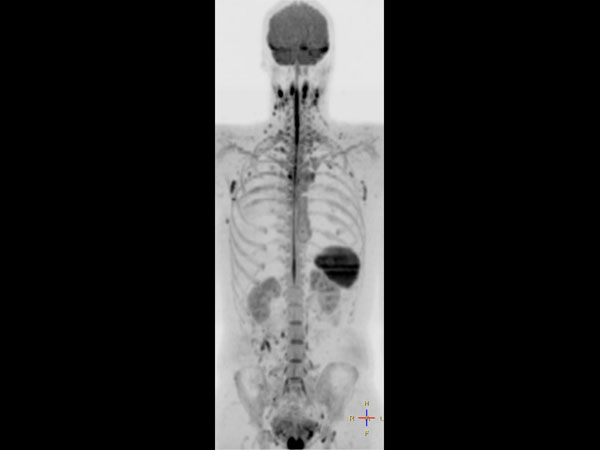

Total Body Imaging

Whole Body imaging